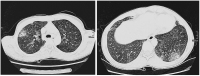

Abbildung 3: Typische periphere Infiltrate einer Patientin mit einer eosinophilen Lungenerkrankung (Churg-Strauss-Syndrom) (siehe Kasuistik 3).

Keywords:

CT

,

eosinophile Lungenerkrankung

Eosinophilie

Thorax